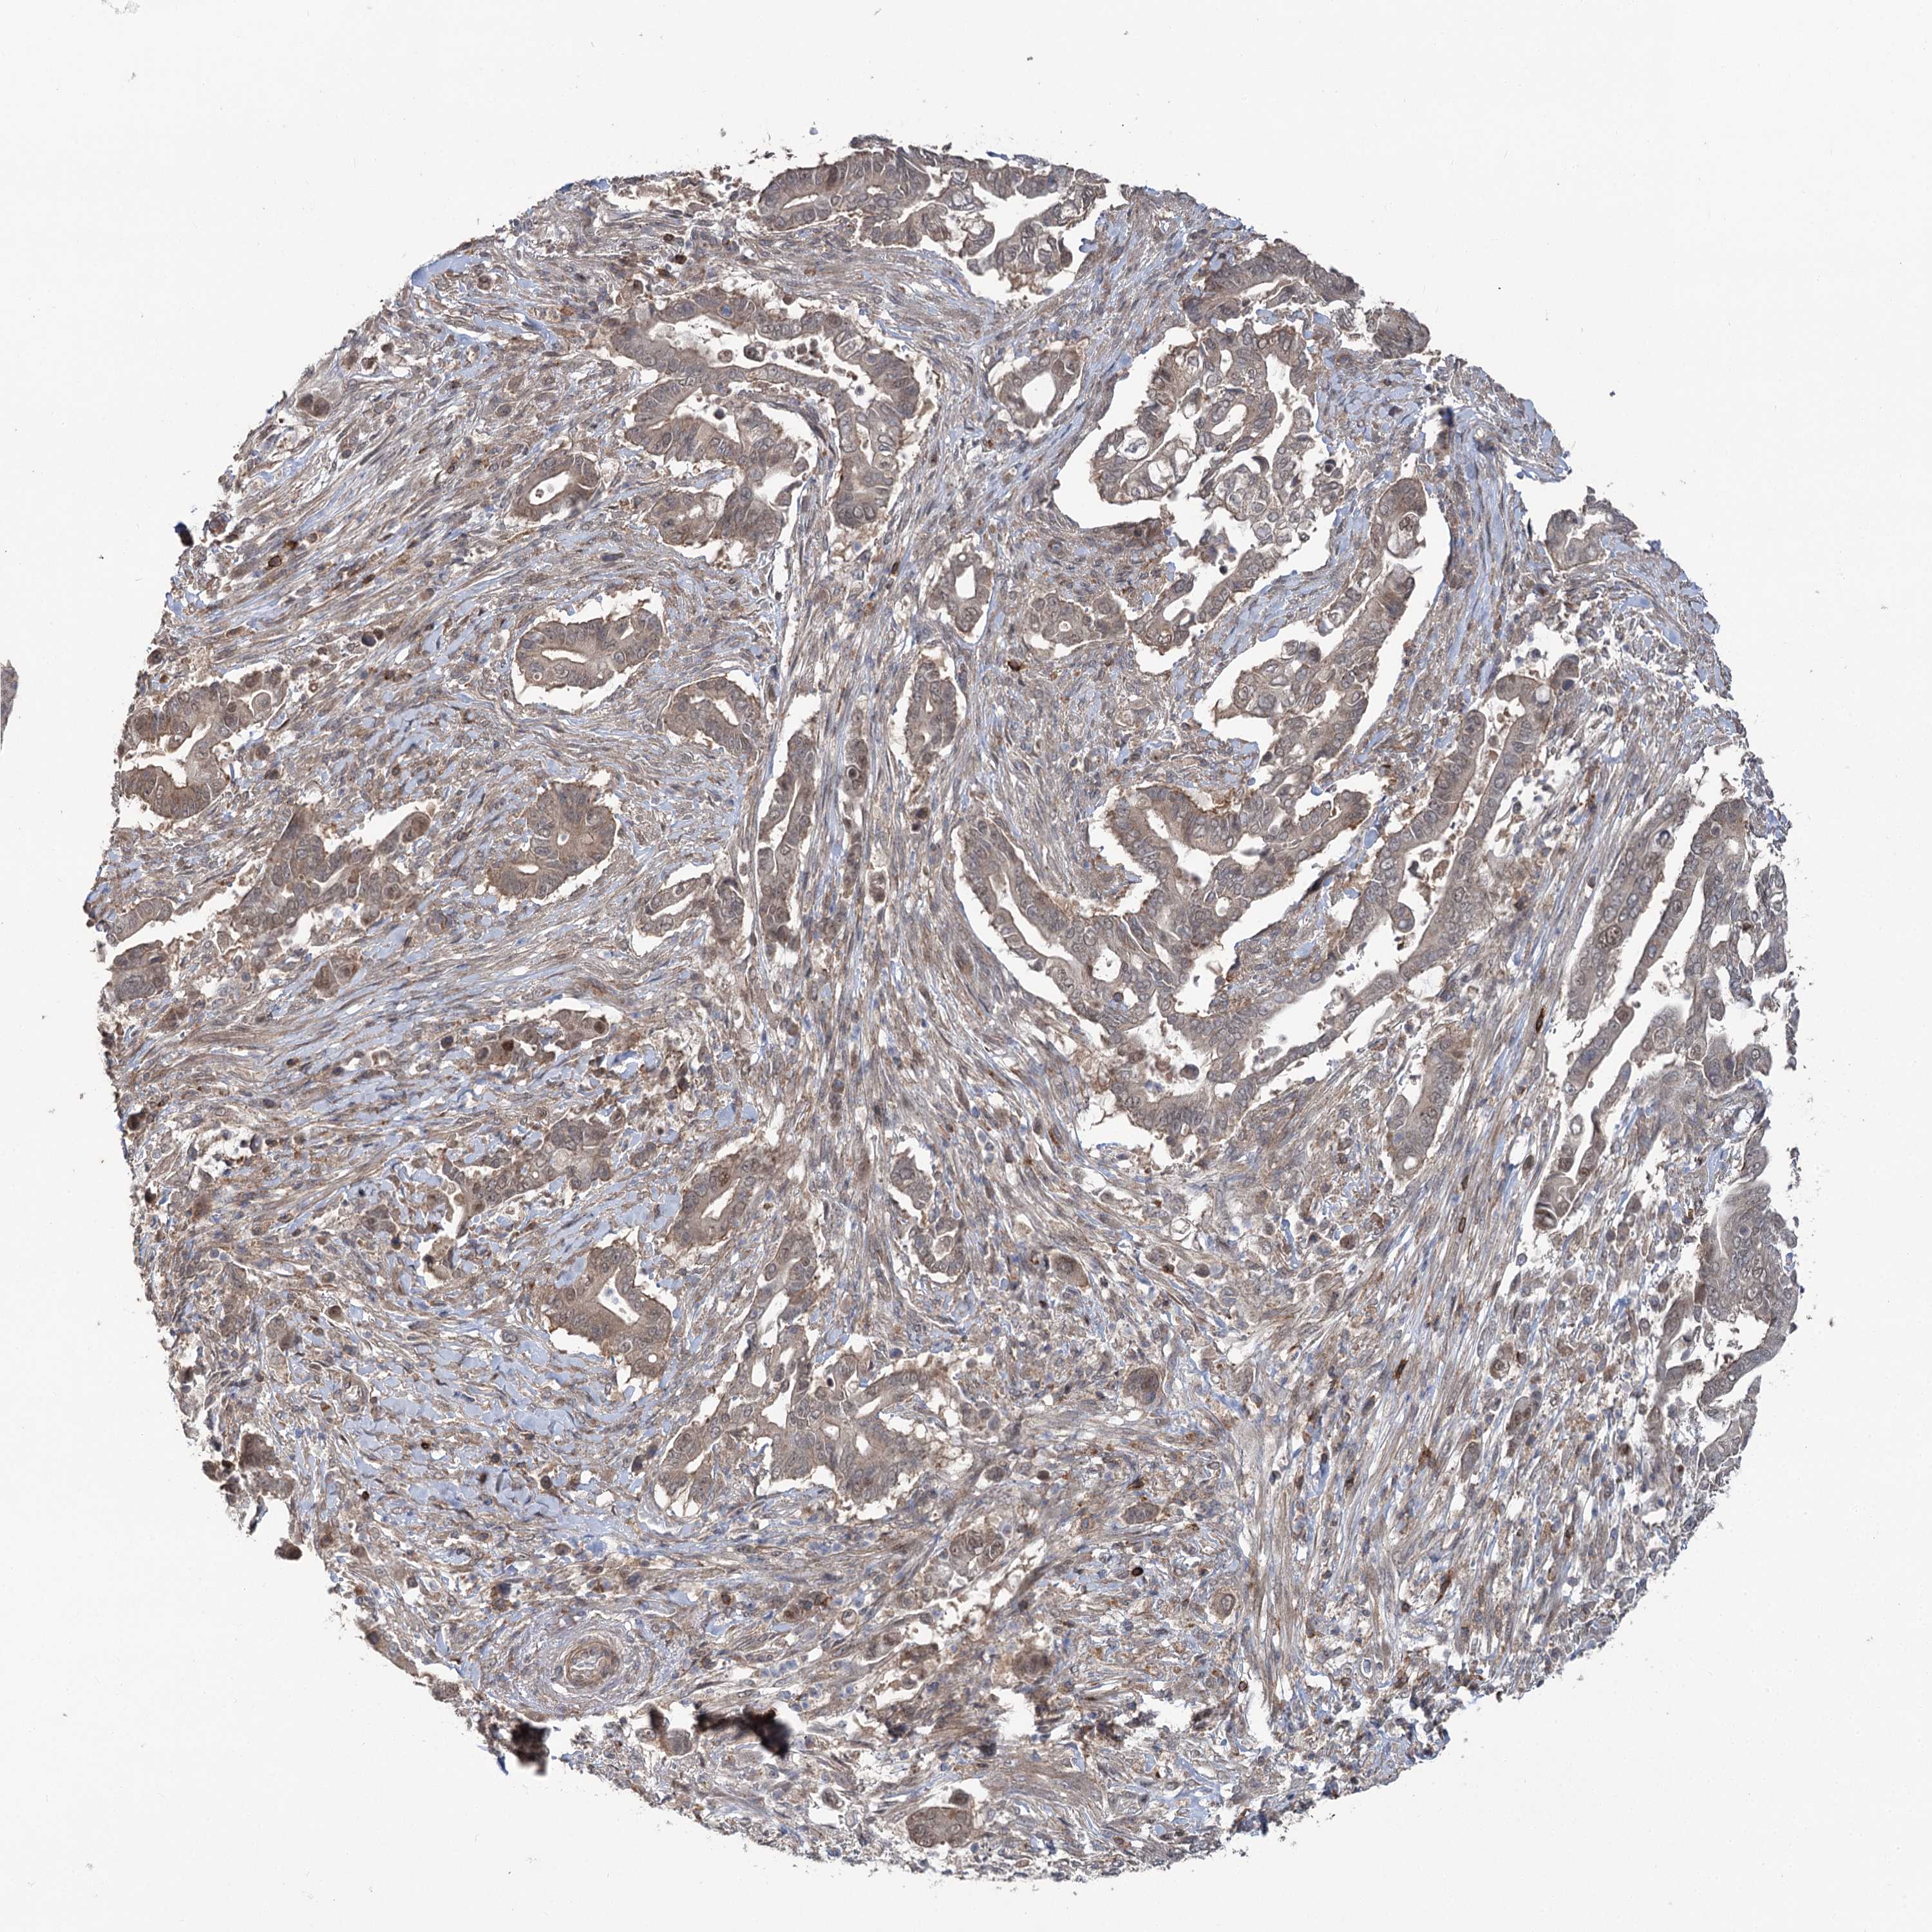

PANCREATIC CANCER - Protein expressioni

A mouse-over function shows sample information and annotation data. Click on an image to view it in a full screen mode. Samples can be filtered based on level of antibody staining by selecting one or several of the following categories: high, medium, low and not detected. The assay and annotation is described here.

Note that samples used for immunohistochemistry by the Human Protein Atlas do not correspond to samples in the TCGA dataset.

Antibody stainingi

Antibody staining in the annotated cell types in the current human tissue is reported as not detected, low, medium, or high, based on conventional immunohistochemistry profiling in selected tissues. This score is based on the combination of the staining intensity and fraction of stained cells.

Each image is clickable and will lead to virtual microscopy that enables deeper exploration of all samples and also displays staining intensity scores, fraction scores and subcellular localization as well as patient and tissue information for each sample.

Antibody HPA038557

Antibody HPA038558

Adenocarcinoma, NOS